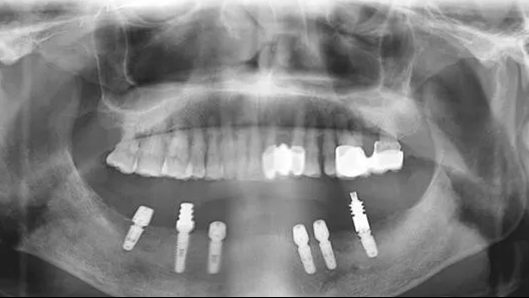

于老伯顺利的种上了六颗品牌种植体,还戴上了固定义齿,结束了他多年缺牙,吃饭不香的苦日子,当天种完后,于老伯就吃上了苹果。吃上自己想吃的食物,心情好了,人看着也年轻了,于老伯露出了满意的笑容。

优点三、该技术只需要植入4-6颗种植体就能恢复半口牙。